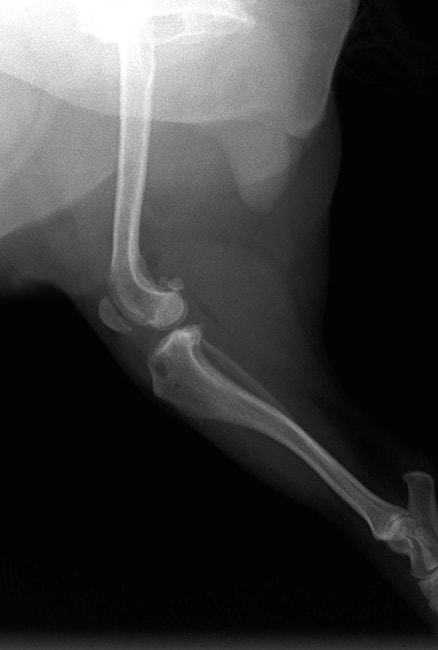

■ 症例22 ポメラニアン 1歳5か月 去勢雄

左後肢の挙上を主訴に来院した。整形学的検査、レントゲン検査より左右の膝蓋骨脱臼(左GradeⅡ〜Ⅲ、右Grade Ⅱ)を認めた。また、脛骨の前方引き出し試験の際に、引き出し兆候は認められないものの、疼痛が認められたため、前十字靭帯の損傷が疑われた。術中における、目視および関節内の操作によって、前十字靭帯の損傷や過伸展といった異常が認められなかったため、膝蓋骨脱臼の整復のみ実施した。手術手技は縫工筋及び内側広筋の解放、脛骨粗面の外側転位、滑車ブロック形造溝術、内外側関節包の縫縮を実施した。本症例は跛行もなく経過良好である。しかし、頸骨高平部の角度(TPA)が 右26.2°、左24.9°であり、解剖学的に前十字靭帯損傷のリスクが高いことから今後の経過に注意が必要である。